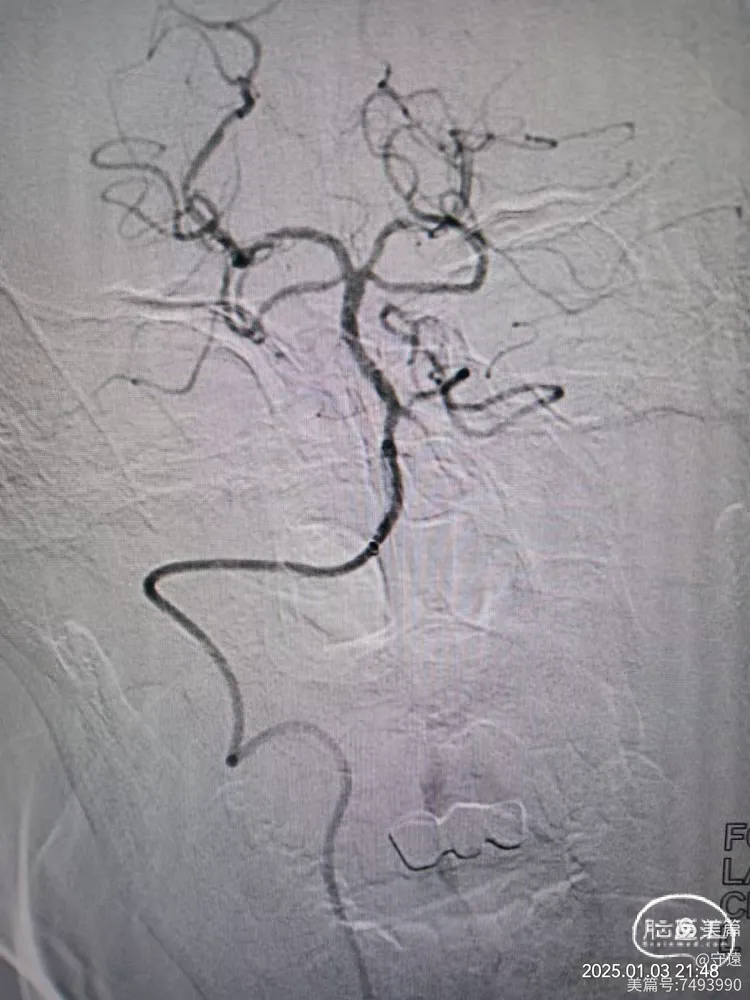

经桡动脉造影:左侧椎动脉起始终部中度狭窄。向颅内供血缓慢,v4段闭塞。

右侧椎动脉为优势椎,血流迟滞,V2以远未显影,考虑V4 闭塞。

右侧椎动脉顺应,更换6F动脉鞘经桡动脉入路行基底动脉开通。